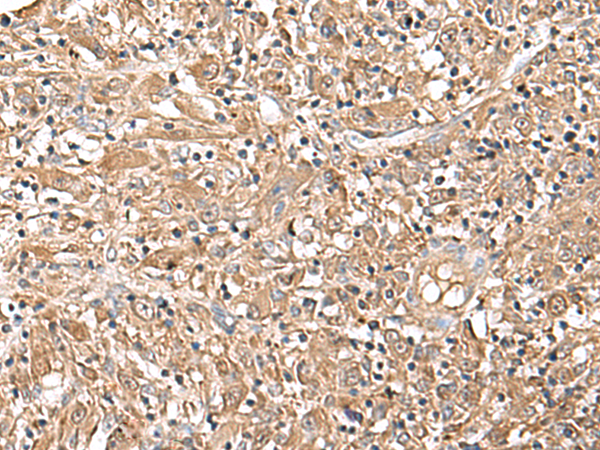

IHC positive control: |

Human liver cancer |